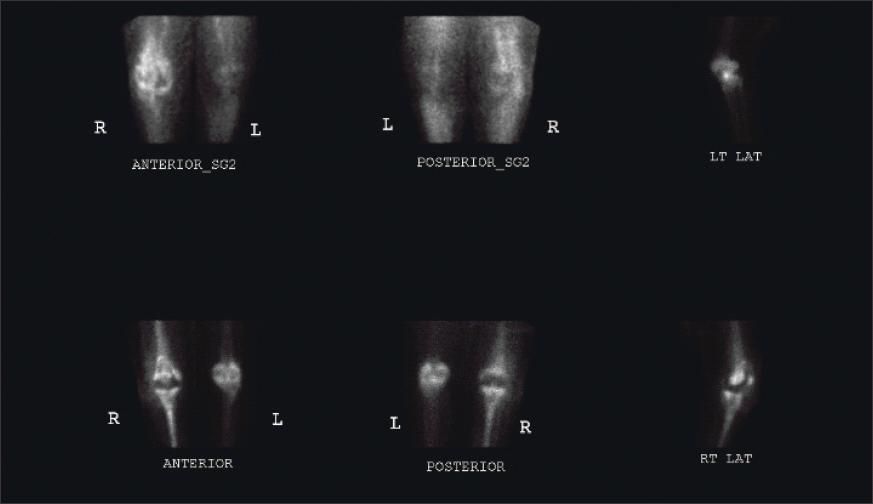

The patient's laboratory workup was remarkable for a C-reactive protein level of 16.68 mg/dL and an erythrocyte sedimentation rate of 31 mm/h. The white blood cell count and differential were normal. A CT scan of the right knee revealed a low density soft tissue mass anterior to the tibial tuberosity, with the bone at this level demonstrating mild irregularity (Figure 1). Triple-phase, technetium- 99m bone scanning showed intense delayed uptake in the right patella and tibia (Figure 2). The cellulitis was treated with vancomycin and nafcillin until culture results were negative for bacteria.

Figure 2 -

Triple-phase, technetium-99m bone scans show intense delayed uptake in the right patella and tibia.